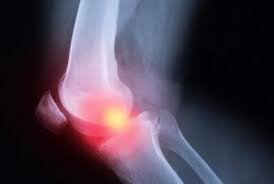

آگاه: دکتر مهران اعظمی، متخصص ارتوپدی و عضو هیئت علمی دانشگاه علوم پزشکی اراک، تاکید کرد: تغییر سبک زندگی، تغذیه نامناسب، چاقی و بیتحرکی باعث شده بسیاری از افراد در سنین پایین، دچار فرسودگی زودرس مفاصل و آرتروز زانو شوند؛ بیماریای که با درد، تورم و محدودیت حرکتی شدید همراه است. وی با اشاره به اینکه آرتروز، در واقع آسیب به غضروفهای مفصلی زانوست که نقش اساسی در تسهیل حرکت استخوانهای ران و ساق دارند، افزود: با افزایش سن یا به دلایل تغذیهای و فیزیکی، این غضروفها نازک شده و باعث بروز دردهای مزمن بهویژه هنگام راهرفتن، نشستن یا بلندشدن میشوند.

متخصصان هشدار میدهند که سبک زندگی امروز، آرتروز زانو را به یک تهدید خاموش برای جوانان تبدیل کرده است.